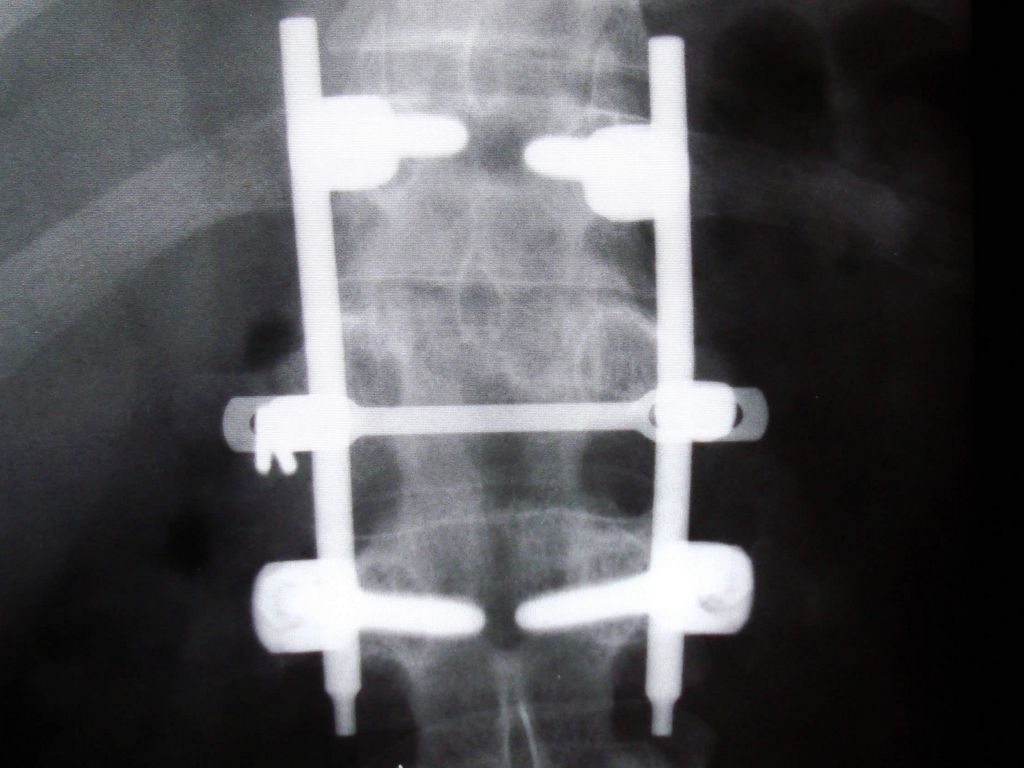

On Spring break in my senior year of high school I convinced my dad to let me travel on my first solo vacation to the beach at Cambria. It was a hard-won victory, but fate crushed this joyous triumph. My vacation turned into a month-long stay in the hospital with a broken back, nearly paralyzed, and a separated knee resulting from a blown tire and a perilous tumble 800 feet down a mountain. I learned at a very young age that every day is precious and tomorrow is not guaranteed.